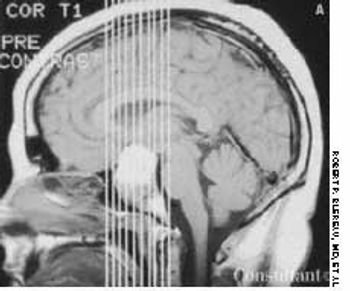

After suffering with recurrent, diffuse, daily headaches for 4 months, a 51-year-old woman sought medical advice. She described the headaches as severe and said they were affected by the position of her head, particularly when bending forward. She also reported episodes of transient numbness on her right side. No syncope was noted, and the patient denied nausea and vomiting.

A 40-year-old woman with a history of amenorrhea complained of recent headaches and galactorrhea for the last 6 months. A neurologic work-up revealed bitemporal hemianopia, and a radiograph of the skull suggested an enlarged sella turcica. A large pituitary adenoma disclosed by an MRI and a serum prolactin level of 360 µg/L led to a diagnosis of prolactinoma.